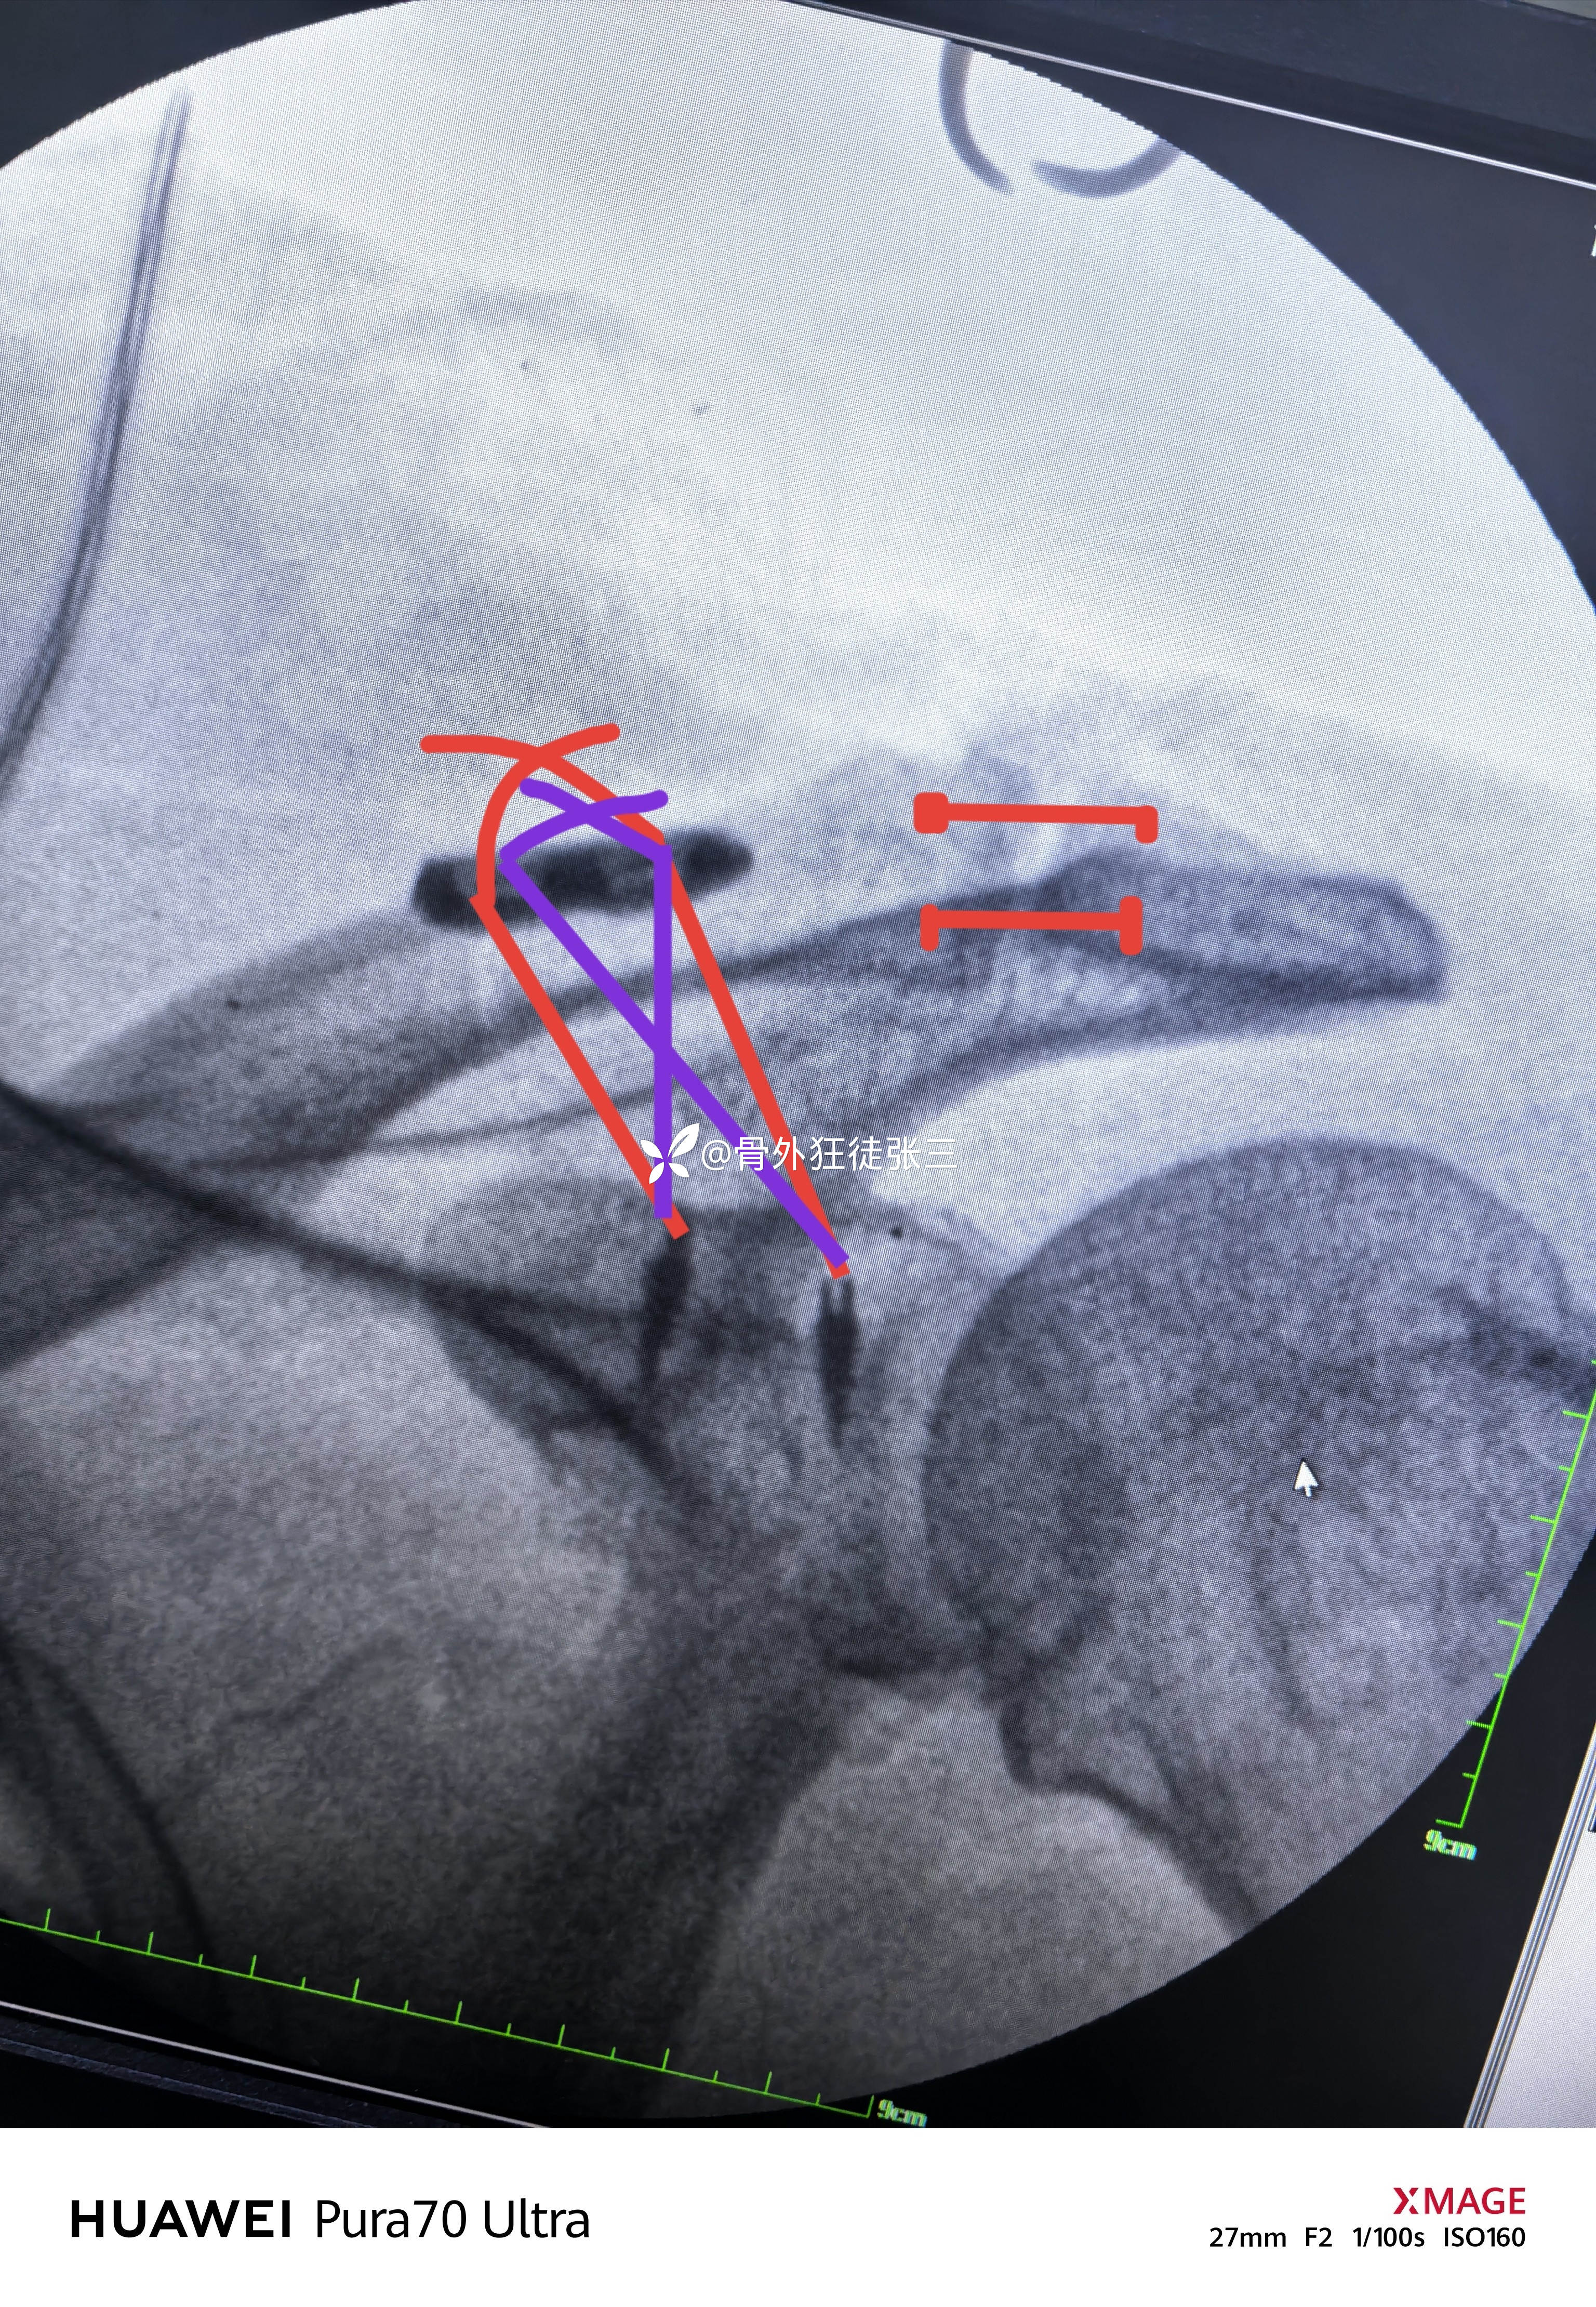

四,微型钛板修剪后保留两个钉孔,建立锁骨两个骨道。

(一般男性为距锁骨远端4.0cm和2cm处,女性为3.5cm和1.5cm处)

(铆钉方向不完美,下次改进)

铆钉线通过钛板孔,分别打结

重建喙锁韧带

肩锁关节打孔

剩余的铆钉线给予重建

双重保障

无比牢固